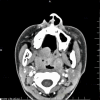

Case presentation: A 13-year-old girl presented with an unexplained sore throat for more than 2 months, together with intermittent fever and suppurative tonsilitis. Nasopharyngoscopy revealed a pharyngeal mass. Enhanced computed tomography (CT) scan showed tonsillar hypertrophy and punctate calcification. Chronic pyogenic granulomatous inflammation with pseudoepithelial squamous epithelial hyperplasia was observed in left tonsil, and pyogenic granulomatous inflammation and a small number of T-lymphoid cells were detected in the right tonsil. The immunohistochemical results showed CD2+, CD3+, CD4+, CD5+, CD8+, granzyme B+, and TIA-1+. The Ki-67 proliferation index was 20%. The case showed T cell receptor gene rearrangement. Finally, the case was diagnosed as ENKTL of stage II with tonsil involvement. The patient received 6 cycles of chemotherapy with SMILE regimen, and showed complete response with no recurrence in the follow-up.